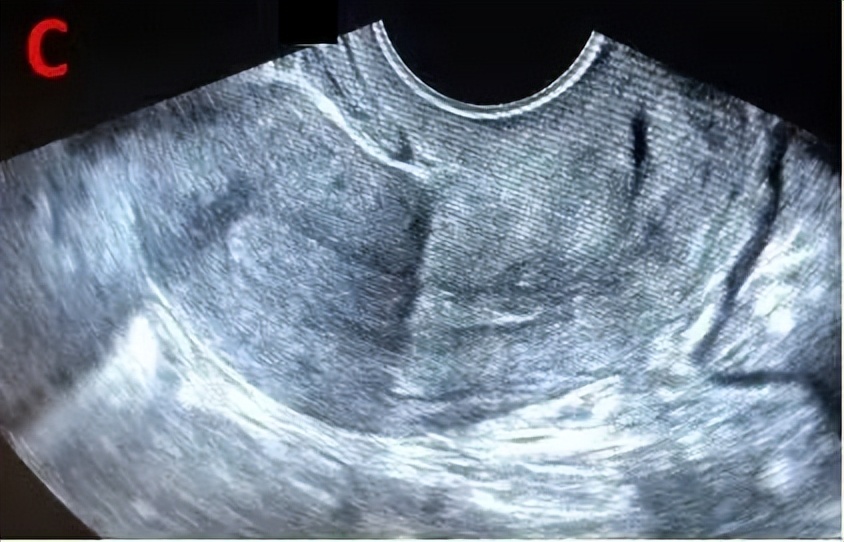

成熟卵泡(月经周期14天左右):卵泡直径达到18-25mm时,外形饱满呈圆形或椭圆形,内壁薄而清晰,位置移向卵巢表面并向外突出,如果卵泡一侧内壁上探及卵丘(出现率约20%),表现为细小点状高回声 ,意味着排卵过程将在24小时内开始。